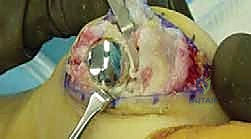

3. استبدال المفصل (Arthroplasty) - الثورة الطبية

- لمن تصلح؟ للمرضى في المراحل المتقدمة (2، 3، وأحياناً 4) الذين يرفضون دمج المفصل ويرغبون بشدة في الحفاظ على حركة المفصل.

- ما هي؟ استبدال أسطح المفصل التالفة بمواد صناعية. وهنا تبرز التقنية الأحدث والأكثر نجاحاً عالمياً: **تقنية Arthrosurface